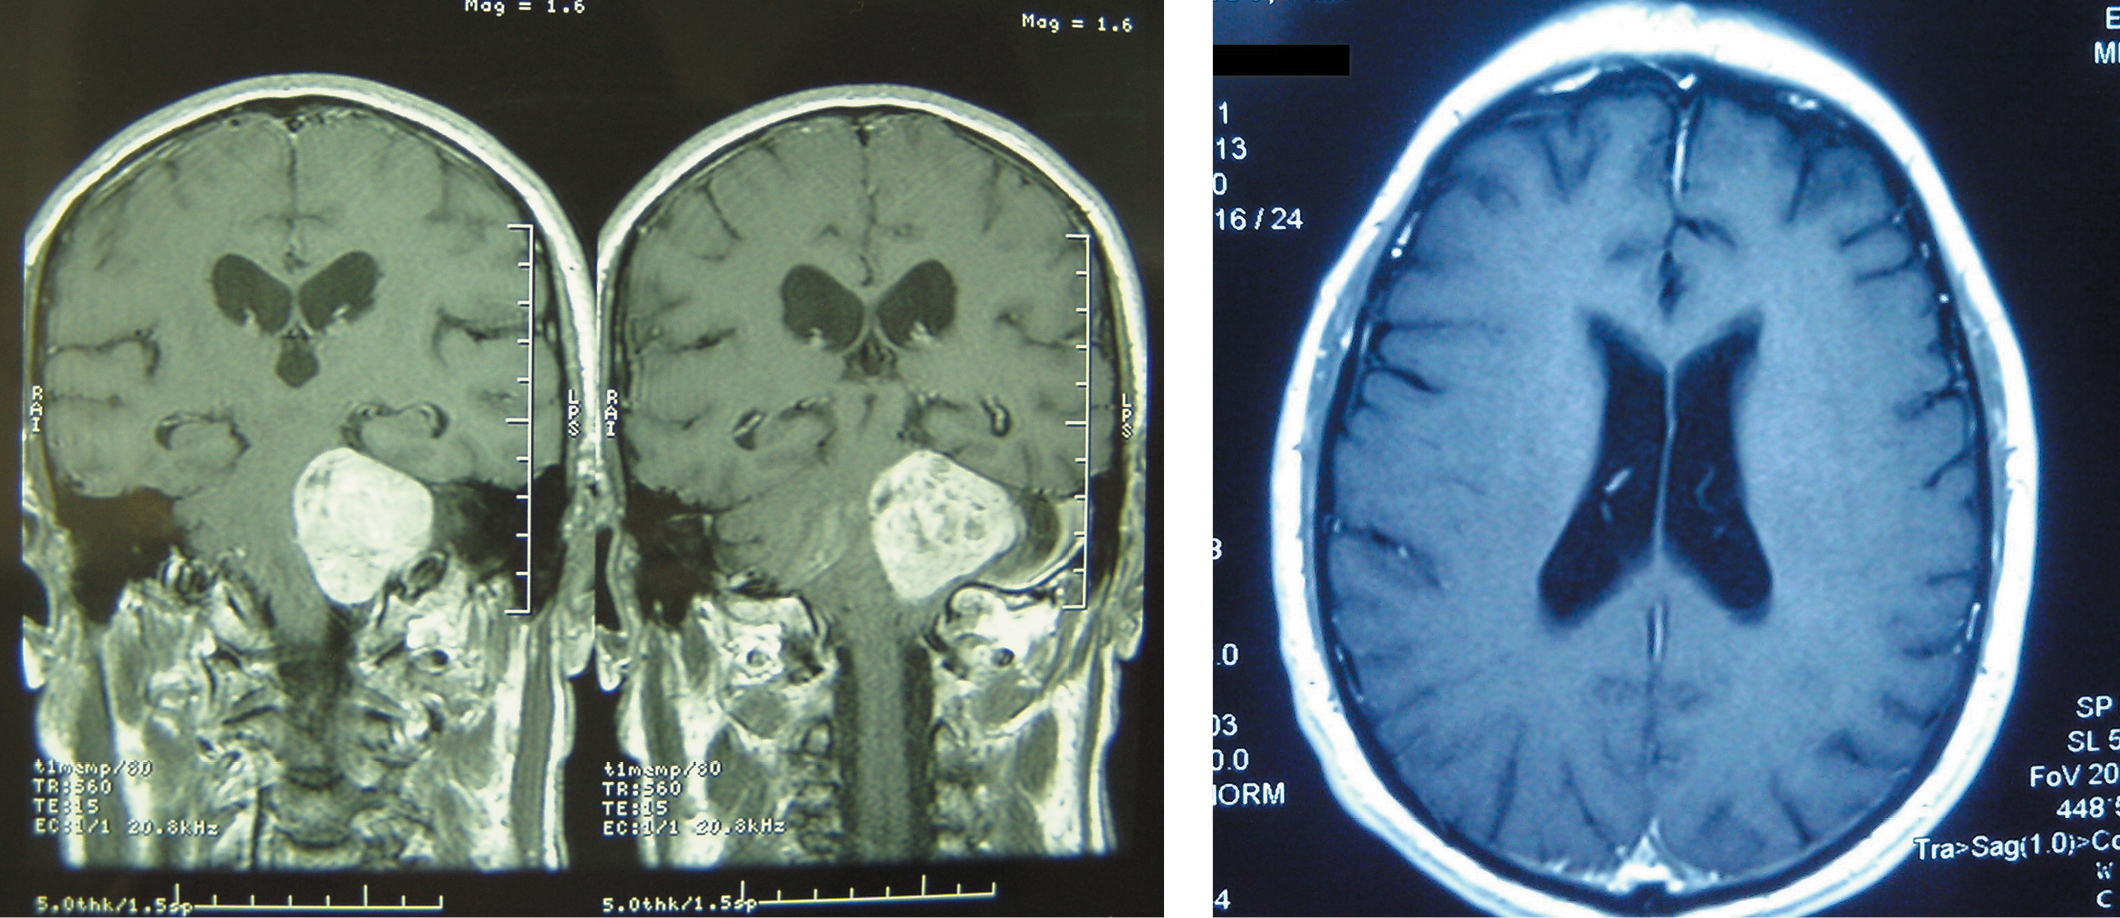

The patient has been experiencing a gradual decrease in hearing in the left ear for 2 years. In 2018, the patient's condition worsened: headache, unsteady gait, dizziness, lacrimation from the left eye, and complete deafness in the left ear developed. Magnetic resonance imaging (MRI scan) of the brain revealed the following: a VS up to 4.6 cm on the left (Fig. 1); severe compression of the pons and the left cerebellar hemisphere; compression and displacement of the fourth cerebellar ventricle; and communicating triventricular hydrocephalus without periventricular edema or girus flattening.

Fig. 1. Preoperative brain MRI of the patient revealed a left cerebellopontine angle tumor with intense inhomogeneous accumulation of paramagnetic contrast agent. Lateral ventricles are dilated. Preoperative coronal and axial contrast-enhanced T1-weighted MR images.